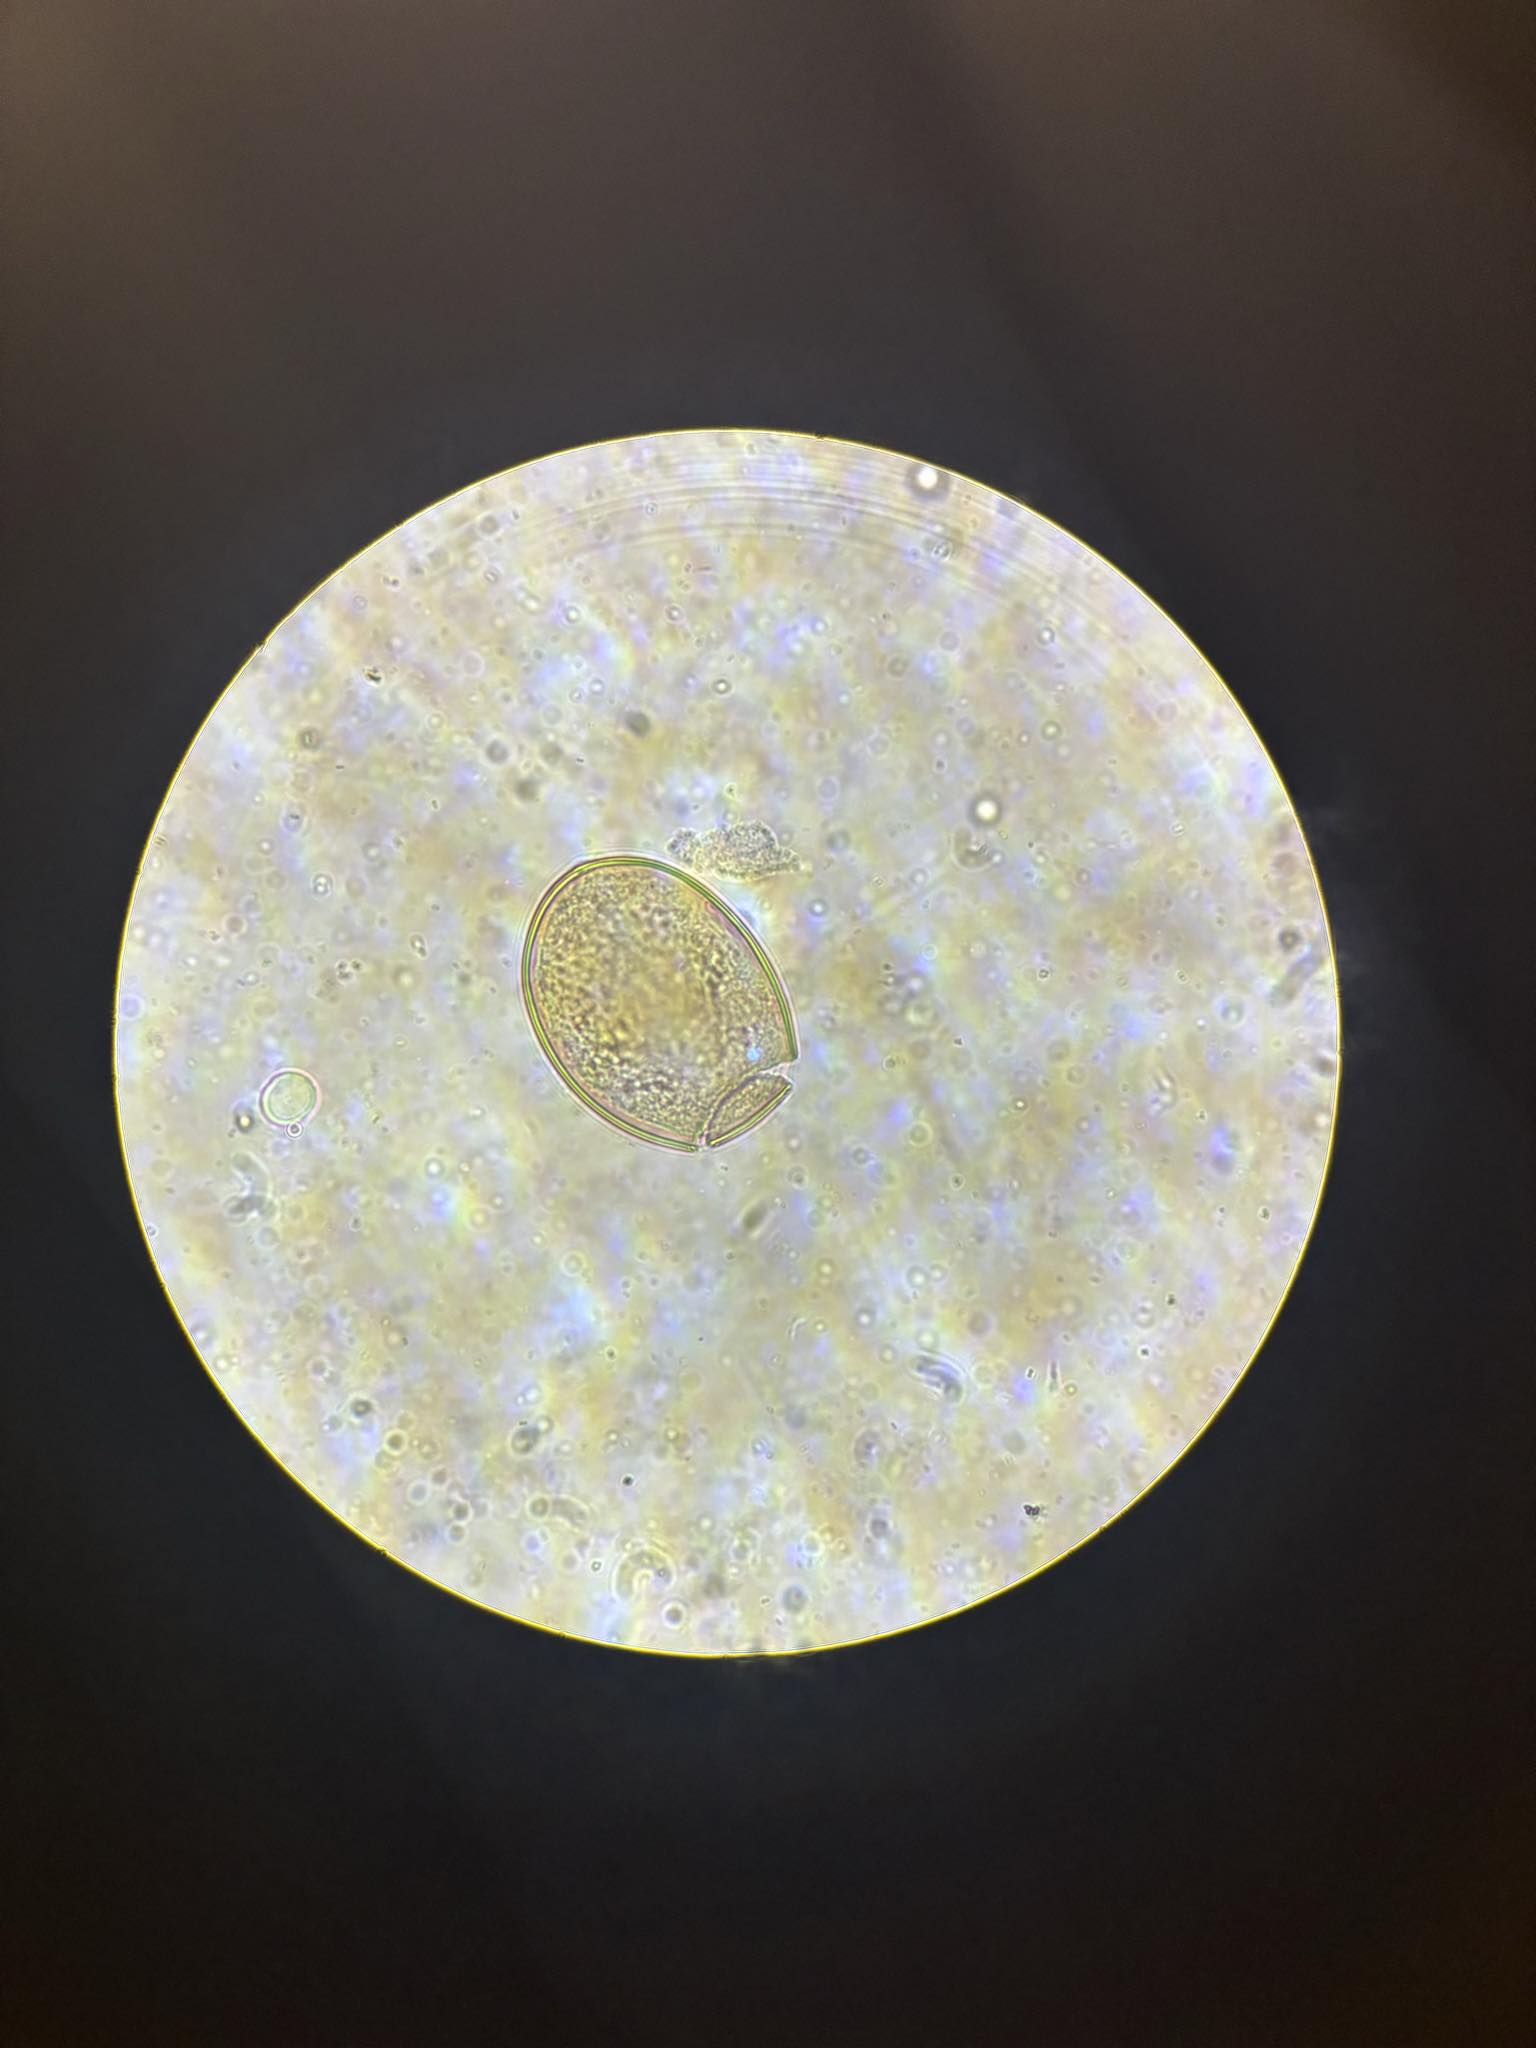

diphhyllobothrium latum jaja

fasciola hepatica/ fasciolopsis buski jajo

fasciolopsis buski jajo